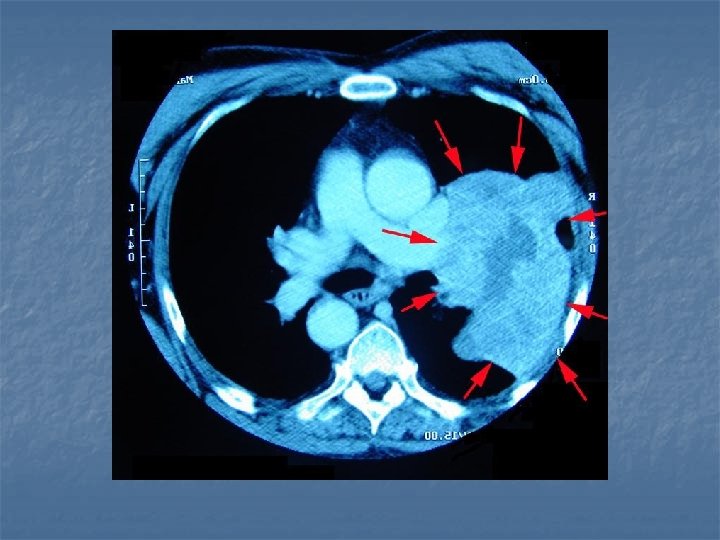

LUNG CANCER - diagnosis n n n X-ray CT scan (computed tomography – a cross-section of the lungs is taken) Helical low-dose CT scan detect very small tumours (see right)